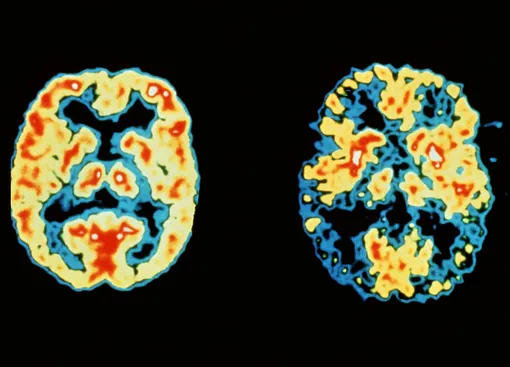

За несколько лет до того, как у человека начинают проявляться первые симптомы болезни Альцгеймера, в его мозге начинают образовываться так называемые β-амилоидные бляшки. Эти бляшки нарушают связь креток мозга, чем впоследствии вызывают снижение когнитивных функций.